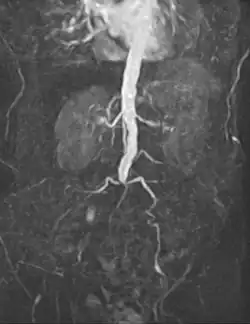

An abdominal aortic aneurysm (AAA) refers to aneurysmal dilation of the aorta confined to the abdominal cavity. Most commonly, aneurysms are asymptomatic and located in the infrarenal position. Often, they are discovered incidentally or on screening exams in patients with risk factors such as a history of smoking. Patients with aneurysms which have a diameter less than 5 cm are at <1% rupture risk per year. When the aneurysm meets size criteria it can be treated with aortic replacement or EVAR.